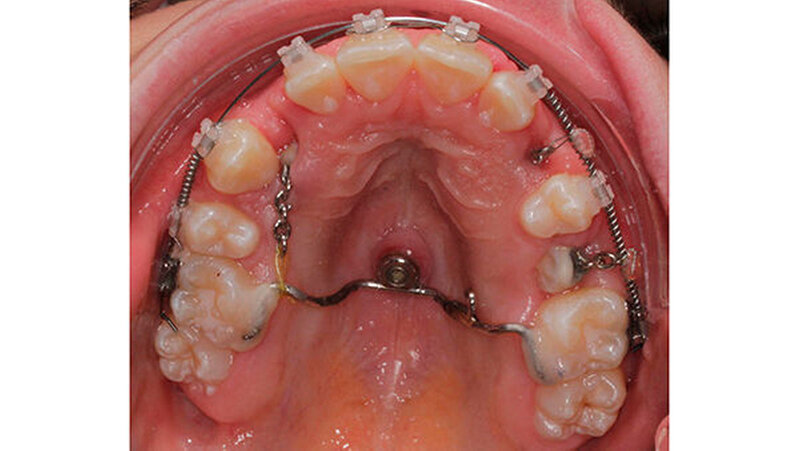

Zur Schaffung einer stabilen Verankerungseinheit wurde zunächst ein Gaumenimplantat inseriert und aufgrund des palatinal verlagerten Prämolaren 14 und des Eckzahns 23 im posterioren Gaumen platziert.

Ein mit dem Implantat verbundener Transpalatinalbogen, welcher adhäsiv an den Sechsjahresmolaren befestigt wurde, sollte letztere in ihrer Position stabilisieren und das während der Extrusion der verlagerten Zähne auf sie wirkende Drehmoment auffangen. Nach der Milchzahnextraktion und der chirurgischen Freilegung von Zahn 14 und 23 begann die kieferorthopädischen Einstellung der Zähne in den Zahnbogen mit geringen, kontinuierlich applizierten Kräften.